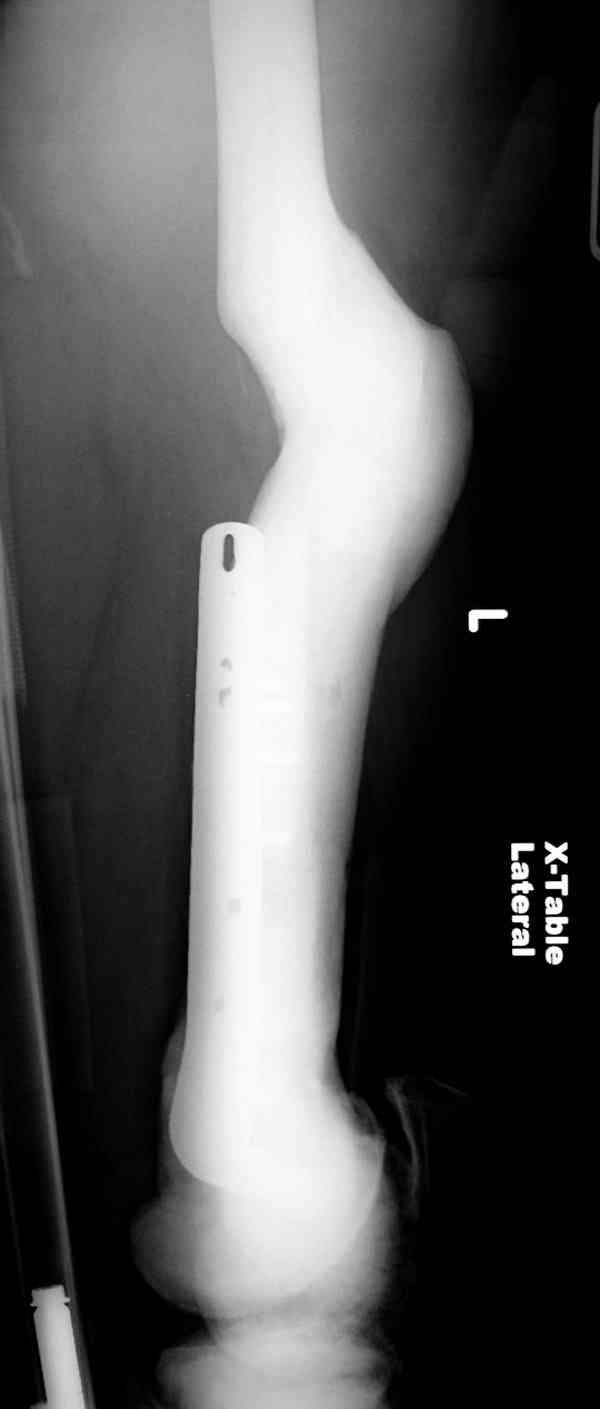

“При лечении переломов у больных с остеопетрозом (в прошлом году был случай) необходимо быть готовым к длительным операциям из-за трудности

обработки традиционными методами "мраморной" кости, иметь в наличие достаточное количество свежих острых инстументов и персонала при необходимости замены (были случаи отстрочки операции на следующий день из-за физической усталости персонала), и надо избежать особо трудоемких операции как интрамедуллярное сверление”.

слайды из прошлегодного случая.

Djoldas Kuldjanov, MD

Department of Orthopedic Surgery

St. Louis University Medical Center